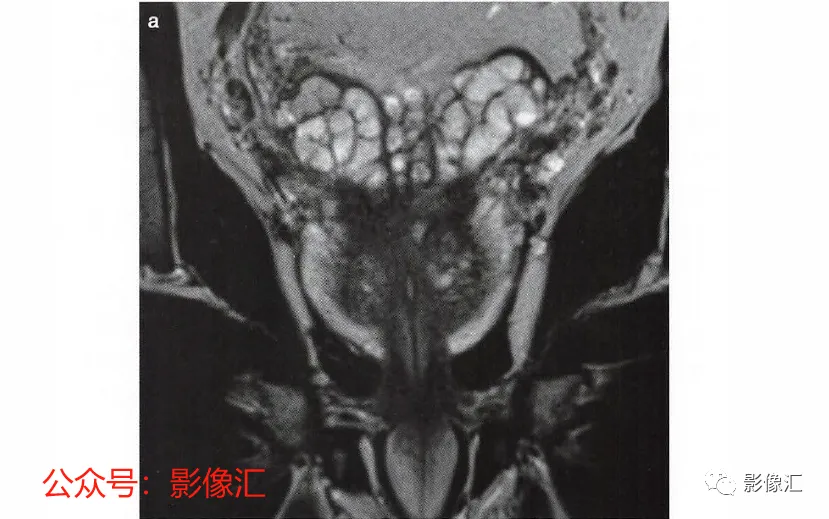

根治性前列腺手术有两个主要目标:完全切除肿瘤和令人满意的术后功能,即控尿及阴茎勃起功能的恢复。为了在根治性前列腺切除术后实现早期控尿恢复,需要完全保留尿道括约肌系统,同时保留耻骨直肠肌和耻骨会阴肌(后者更为重要)。EUS的保存始于在腺体顶端前外侧上彻底分离EUS裙,向尾部方向操作。根据尿道周围筋膜,可正确识别和分离尿道膜部的EUS,这是阴茎海绵体和尿道海绵体神经未梢的位置(图2.12 至图2.14) 。AFMS和前列腺尖部的MRI评估可以显示这些区域中存在肿瘤,或者为主要病灶区域,或者更常见的是,MRI可以显示最初其他解剖区域的肿瘤对AFMS和(或)前列腺尖部的局部累及。这些情况下,在这个水平由于造成阳性切缘的风险很高,因此括约肌保留手术是禁忌的。

- 对前列腺尖部精确的MRI评估将使我们能够在手术过程中完全切除肿瘤并获得令人满意的术后功能结果,即恢复早期控尿和阴茎勃起功能。